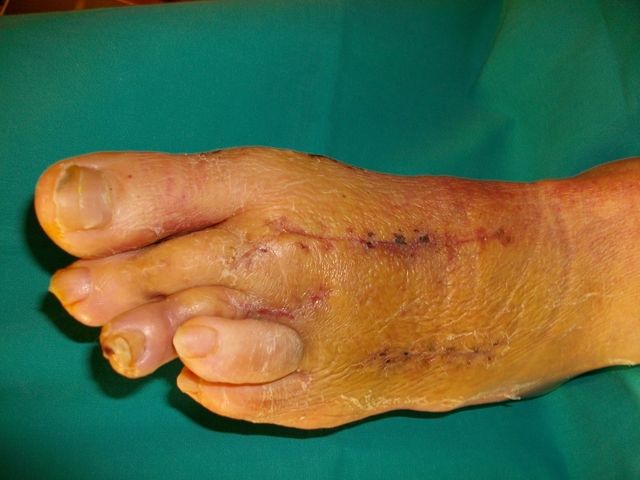

Hallux valgus intervenidos